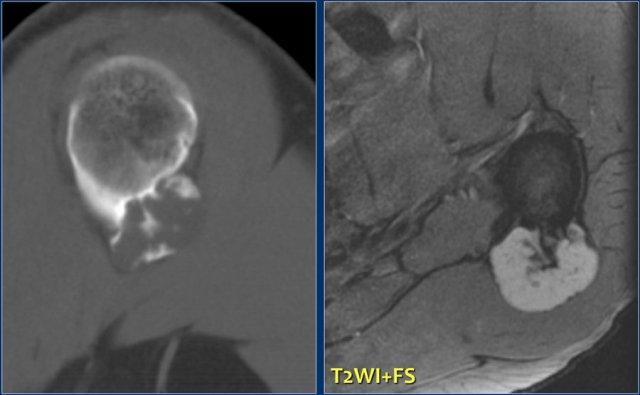

Đây là hình ảnh khối u vôi hóa một phần áp sát đầu trên xương cánh tay với sự xâm lấn vỏ xương trên ảnh CT cắt ngang.

Hình ảnh MRI trọng số T2 cho thấy một khối u thùy với cường độ tín hiệu cao.

Khoang tủy xương không bị xâm lấn, điều này rất quan trọng cho chiến lược phẫu thuật.

U sụn màng xương có thể có các đặc điểm hình ảnh tương tự, tuy nhiên, hầu như luôn nhỏ hơn nhiều.

Phim X-quang thường ở một bệnh nhân khác cho thấy tổn thương vôi hóa không đều với hiện tượng nâng cao màng xương và xâm lấn vỏ xương. Bên phải là hình ảnh T2-WI có FS của cùng bệnh nhân. Khối u cạnh vỏ xương có tín hiệu cao và bờ thùy múi. Chẩn đoán phân biệt: sarcoma sụn cạnh vỏ xương, sarcoma xương cạnh màng xương.